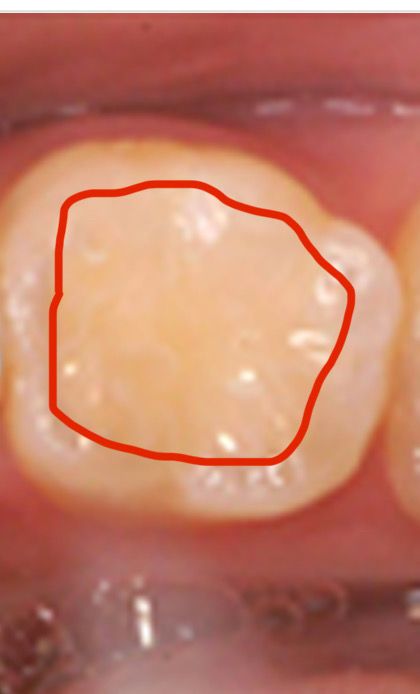

사진은 예시로 첨부해뒀는데, 제가 빨갛게 선 그린 부분이 투명? 회색빛으로, 약간 치아가 속이 비치는? 것처럼 보인다고 생각해주시면 될 것 같습니다. 윗니 포함 모든 치아가 그렇습니다. 그 외에 육안상 별다른 특징은 없습니다.

사진으로 봤을 경우에는 크게 충치가 있어 보이진 않습니다. 하지만 인접면의 충치는 육안으로 보이지 않고 엑스레이상으로만 보이는 경우도 있습니다. 충치의 여부를 확인하기 위해서는 치과에서 진료를 받아보는 거의 좋습니다.

사진에 보이는건 충치는 아니고 탄산음료등으로 인해서 치아 표면이 탈회된상태 같습니다. 그리고 탄산음료는 자주 드시면 치아 사이에 충치가 생길 가능성이 높습니다.

사진을 봐서는 충치라고 단정하긴 어려운데요